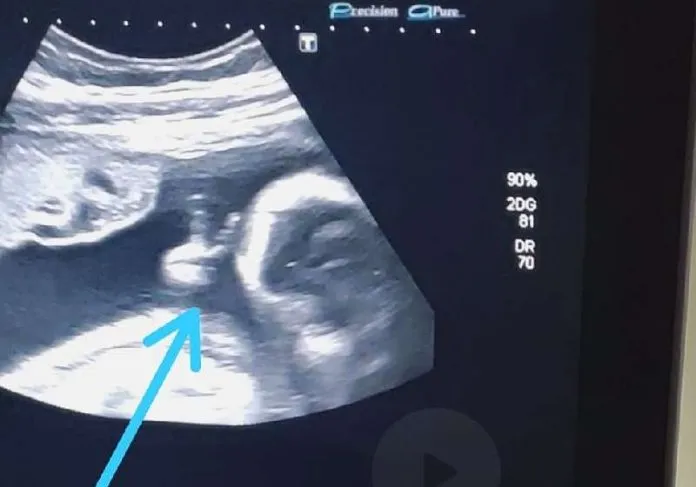

Ao acompanhar o exame de ultrassonografia de sexto mês do primeiro filho, o futuro pai viu o filho fazendo o ‘V de vitória’ com a mãozinha, dentro do útero e ficou chocado com a cena.

“Até a médica falou: ‘olha, ele fez o sinalzinho de vitória com a mão’. Eu fiquei sem acreditar”, contou.